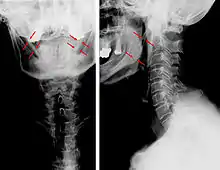

| Anteroposterior and lateral radiographs of cervical spine showing ossification of the stylohyoid ligament on both sides | |

CT scan, coronal section showing bilateral extended styloid process and stylohyoid ligament ossification (incidental finding)